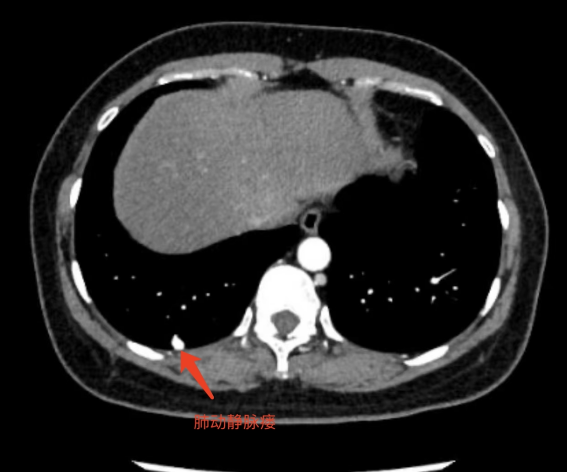

位于肺表面的肺动静脉瘘

肺动静脉瘘多为先天性肺血管畸形,表现为患者的肺动脉和静脉之间的正常血管结构出现异常,血管扩张迂曲或形成海绵状血管瘤,肺动脉血液不经过肺泡直接流入肺静脉,肺动脉与静脉直接相通形成短路。